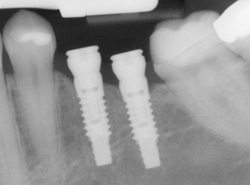

Single or Multiple Implants

Implants are versatile. If you are only missing one tooth, one implant plus one replacement tooth will do the trick. If you are missing several teeth in a row, a few strategically placed implants can support a permanent bridge (a set of replacement teeth). Similarly, if you have lost all of your teeth, a full bridge or full denture can be permanently fixed in your mouth with a strategic number of implants.

Computer Enhanced Treatment Planning We have special software on our computer that allows us to evaluate your dental CT scan in three dimensions for bone quality, bone quantity, and bone location for the best possible placement of your dental implants. This also allows us to work closely and smoothly with your restorative dentist to ensure an ideal result where your dental implants are concerned.